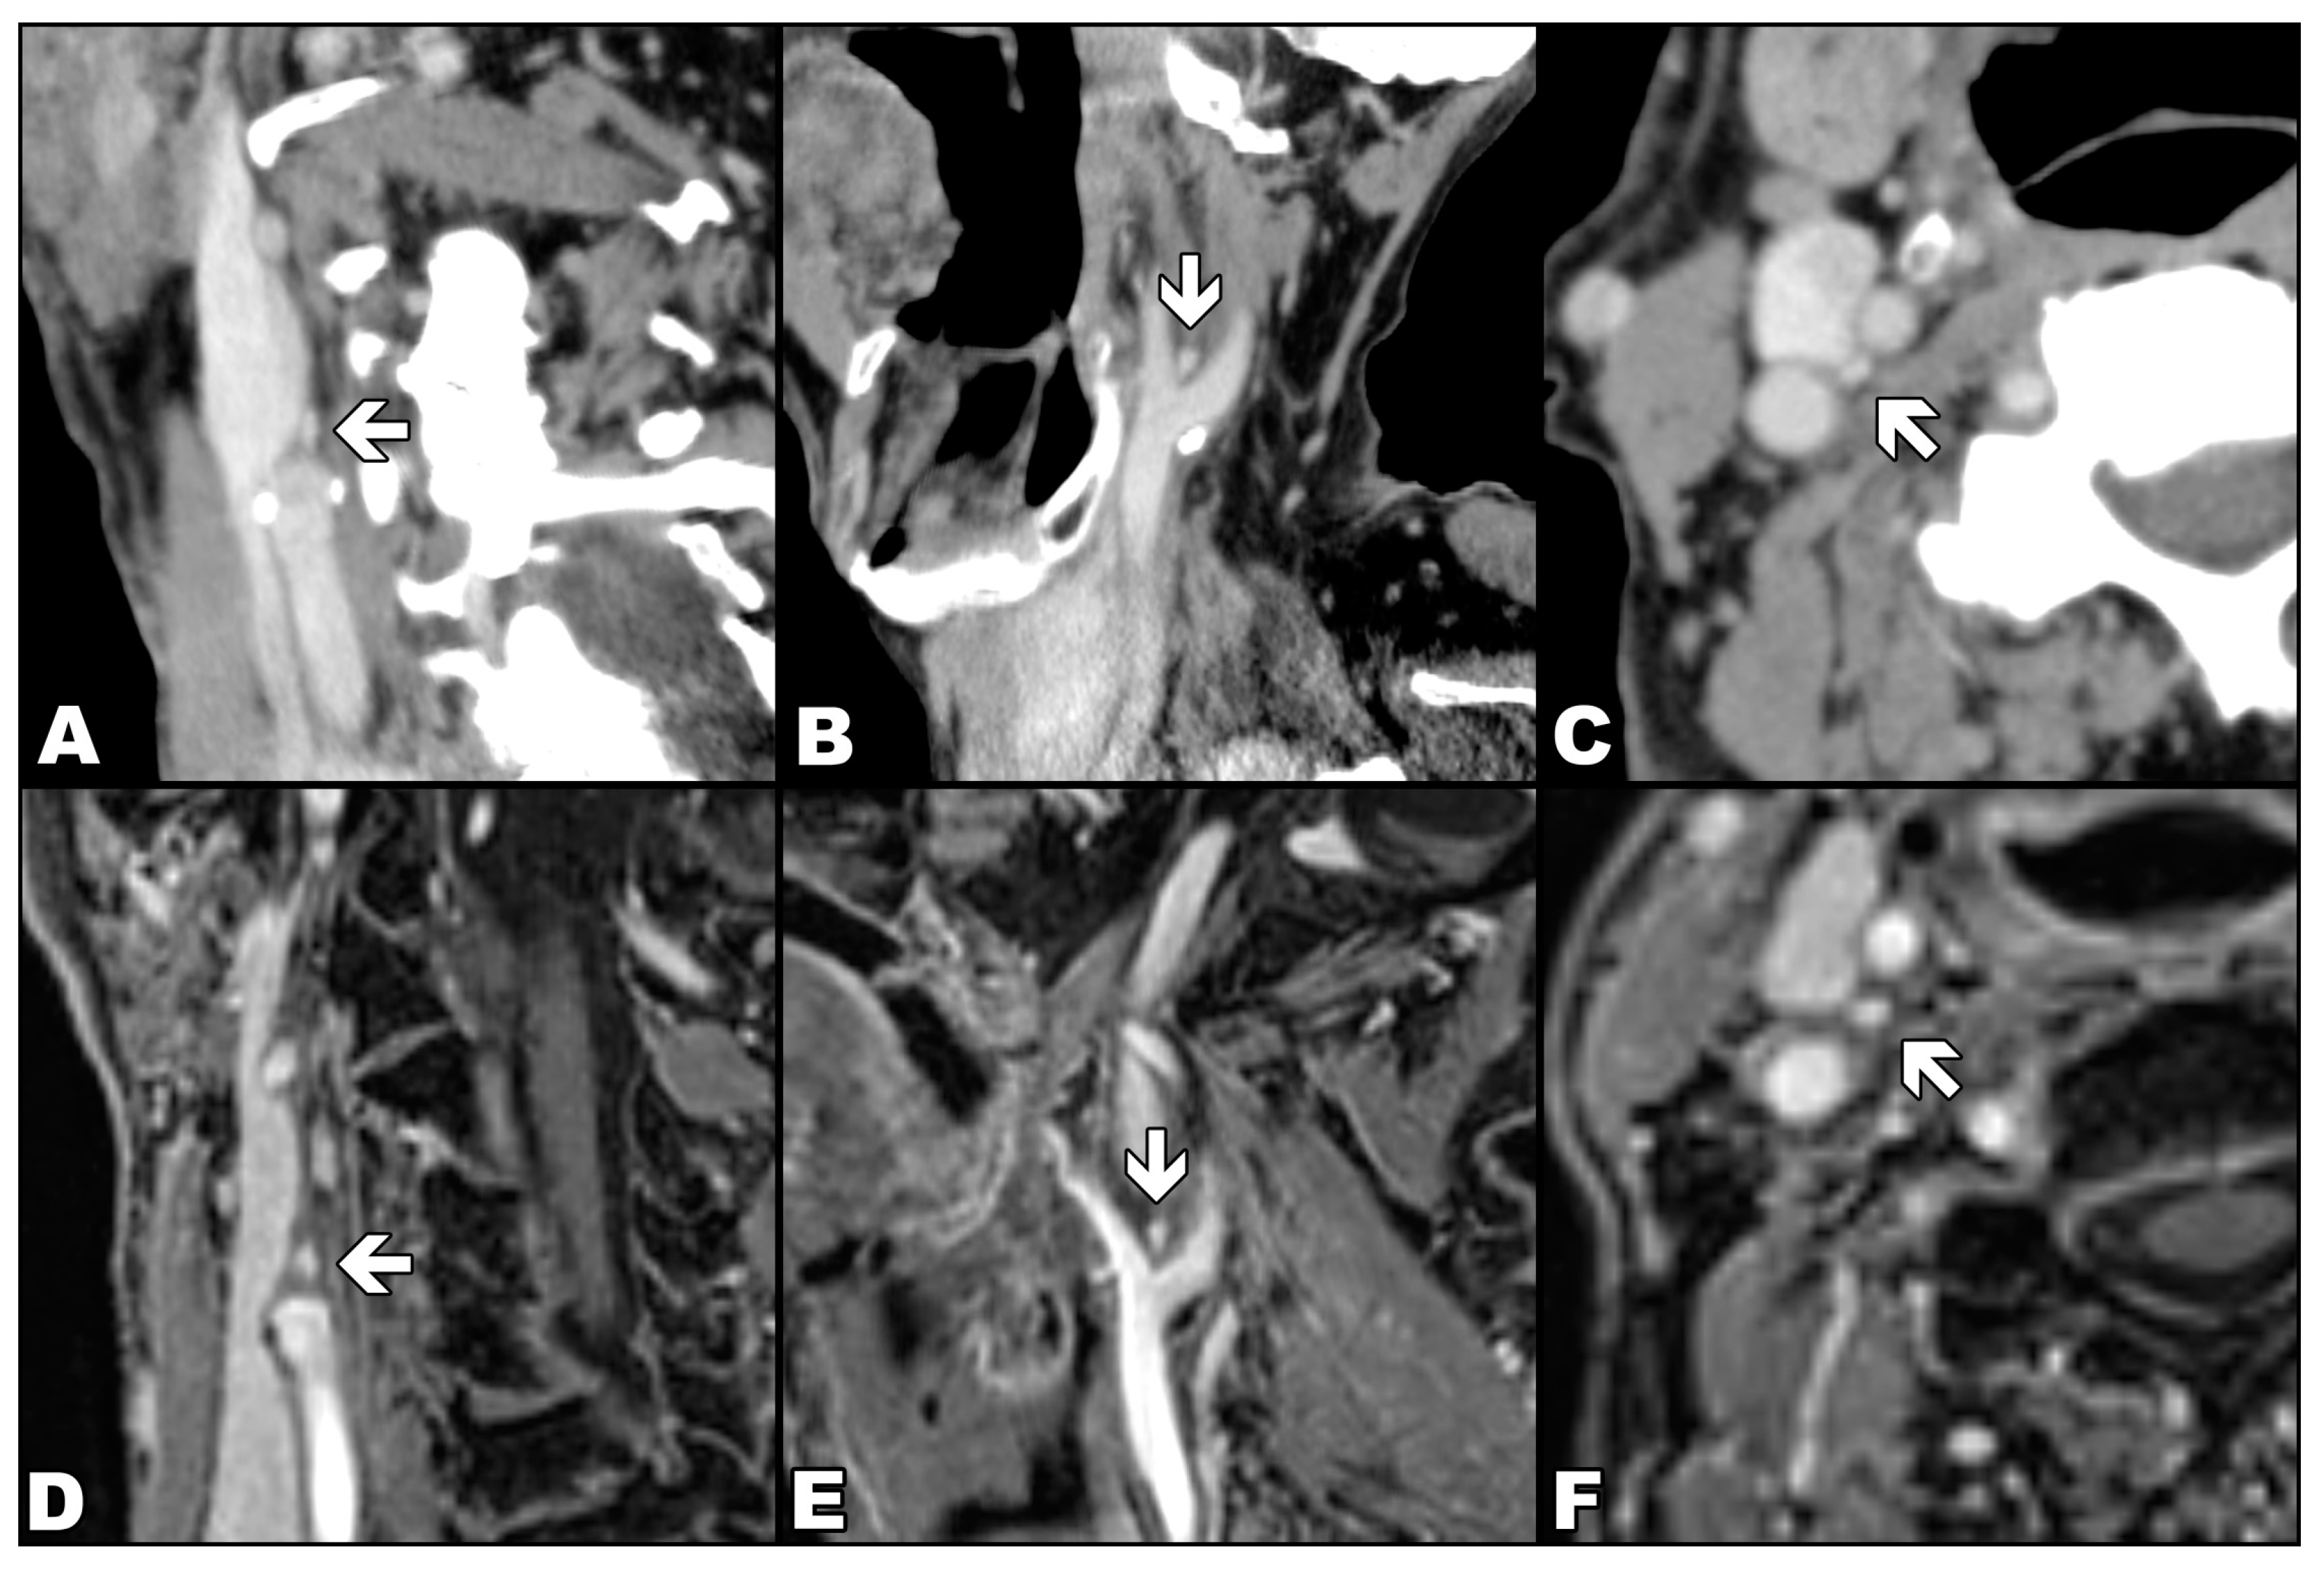

Figure 2.

Comparison of the appearance of the carotid body (arrows) in contrast-enhanced computed tomography (upper row) with the appearance in contrasted-enhanced VIBE sequence in T1-weighted image with Dixon technique in the water-only images (lower row). Computed tomography (images (A–C)) and magnetic resonance (images (D–E)) examinations show the carotid body in three orthogonal planes: oblique coronal (A,D), oblique sagittal (B,E) and axial (C,F).